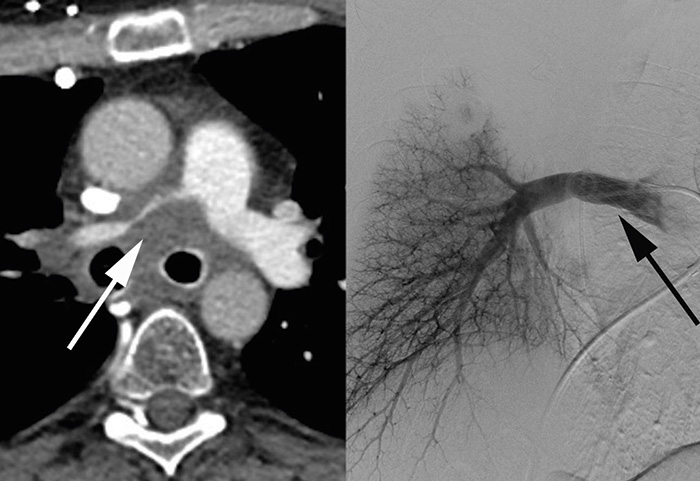

Avlastning med endoskopisk teknik av intrahepatiska gallvägar vid tumörförträngning är ofta inte möjlig, och perkutan inläggning av dränagekateter och/eller stent med interventionell radiologisk teknik är ett återstående alternativ. Perkutan rekanalisering med stent av tumöravstängd vena portae (Figur 1), eller vena lienalis, kan påtagligt reducera risken för blödning från ventrikel eller esofagusvaricer.

Figur 1. Pankreascancer. Övre bilden visar förträngd vena portae samt konfluens av vena lienalis och vena mesenterica superior (pil). Undre bilden visar vena portae (tjock svart pil), vena mesenterica superior (tunn svart pil) och vena lienalis (vit pil) öppnade med stentar.